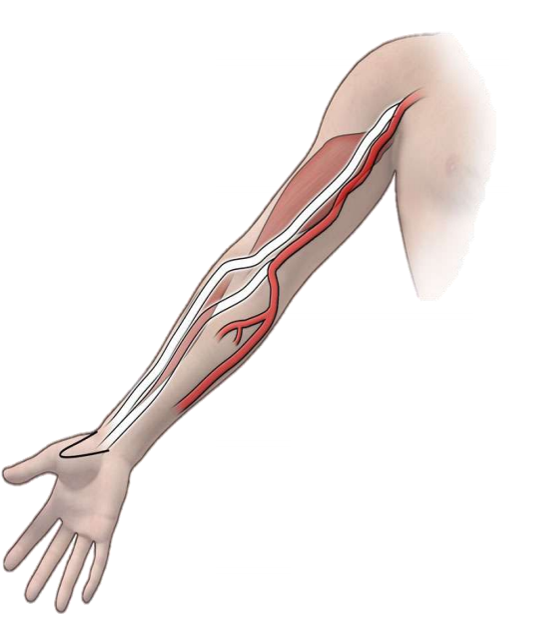

鼻烟区解剖 Anatomical snuffbox

鼻烟区的边界 拇长伸肌后侧 拇短伸肌和拇长外展肌前方的肌腱 桡动脉入路相较于股动脉入路的优势桡动脉影像学正常解刨

桡动脉通路与股动脉通路的比较优势 没有相邻的重要结构 6 易于压缩的 主要血管接入部位的并发症减少了 65% 患者偏好 无需卧床休息 较少受到肥胖的影响 桡动脉变异桡动脉解刨变异